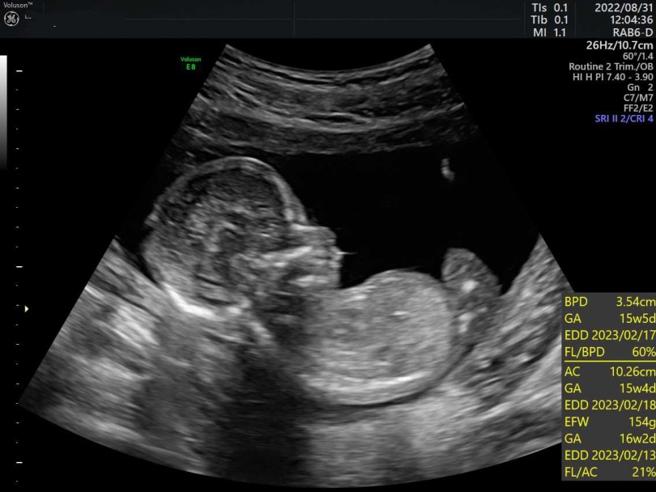

小美在今年8月懷上身孕後即遭到長官同事的冷言冷語霸凌,原本穩定的工作也變了調。(圖/讀者提供)